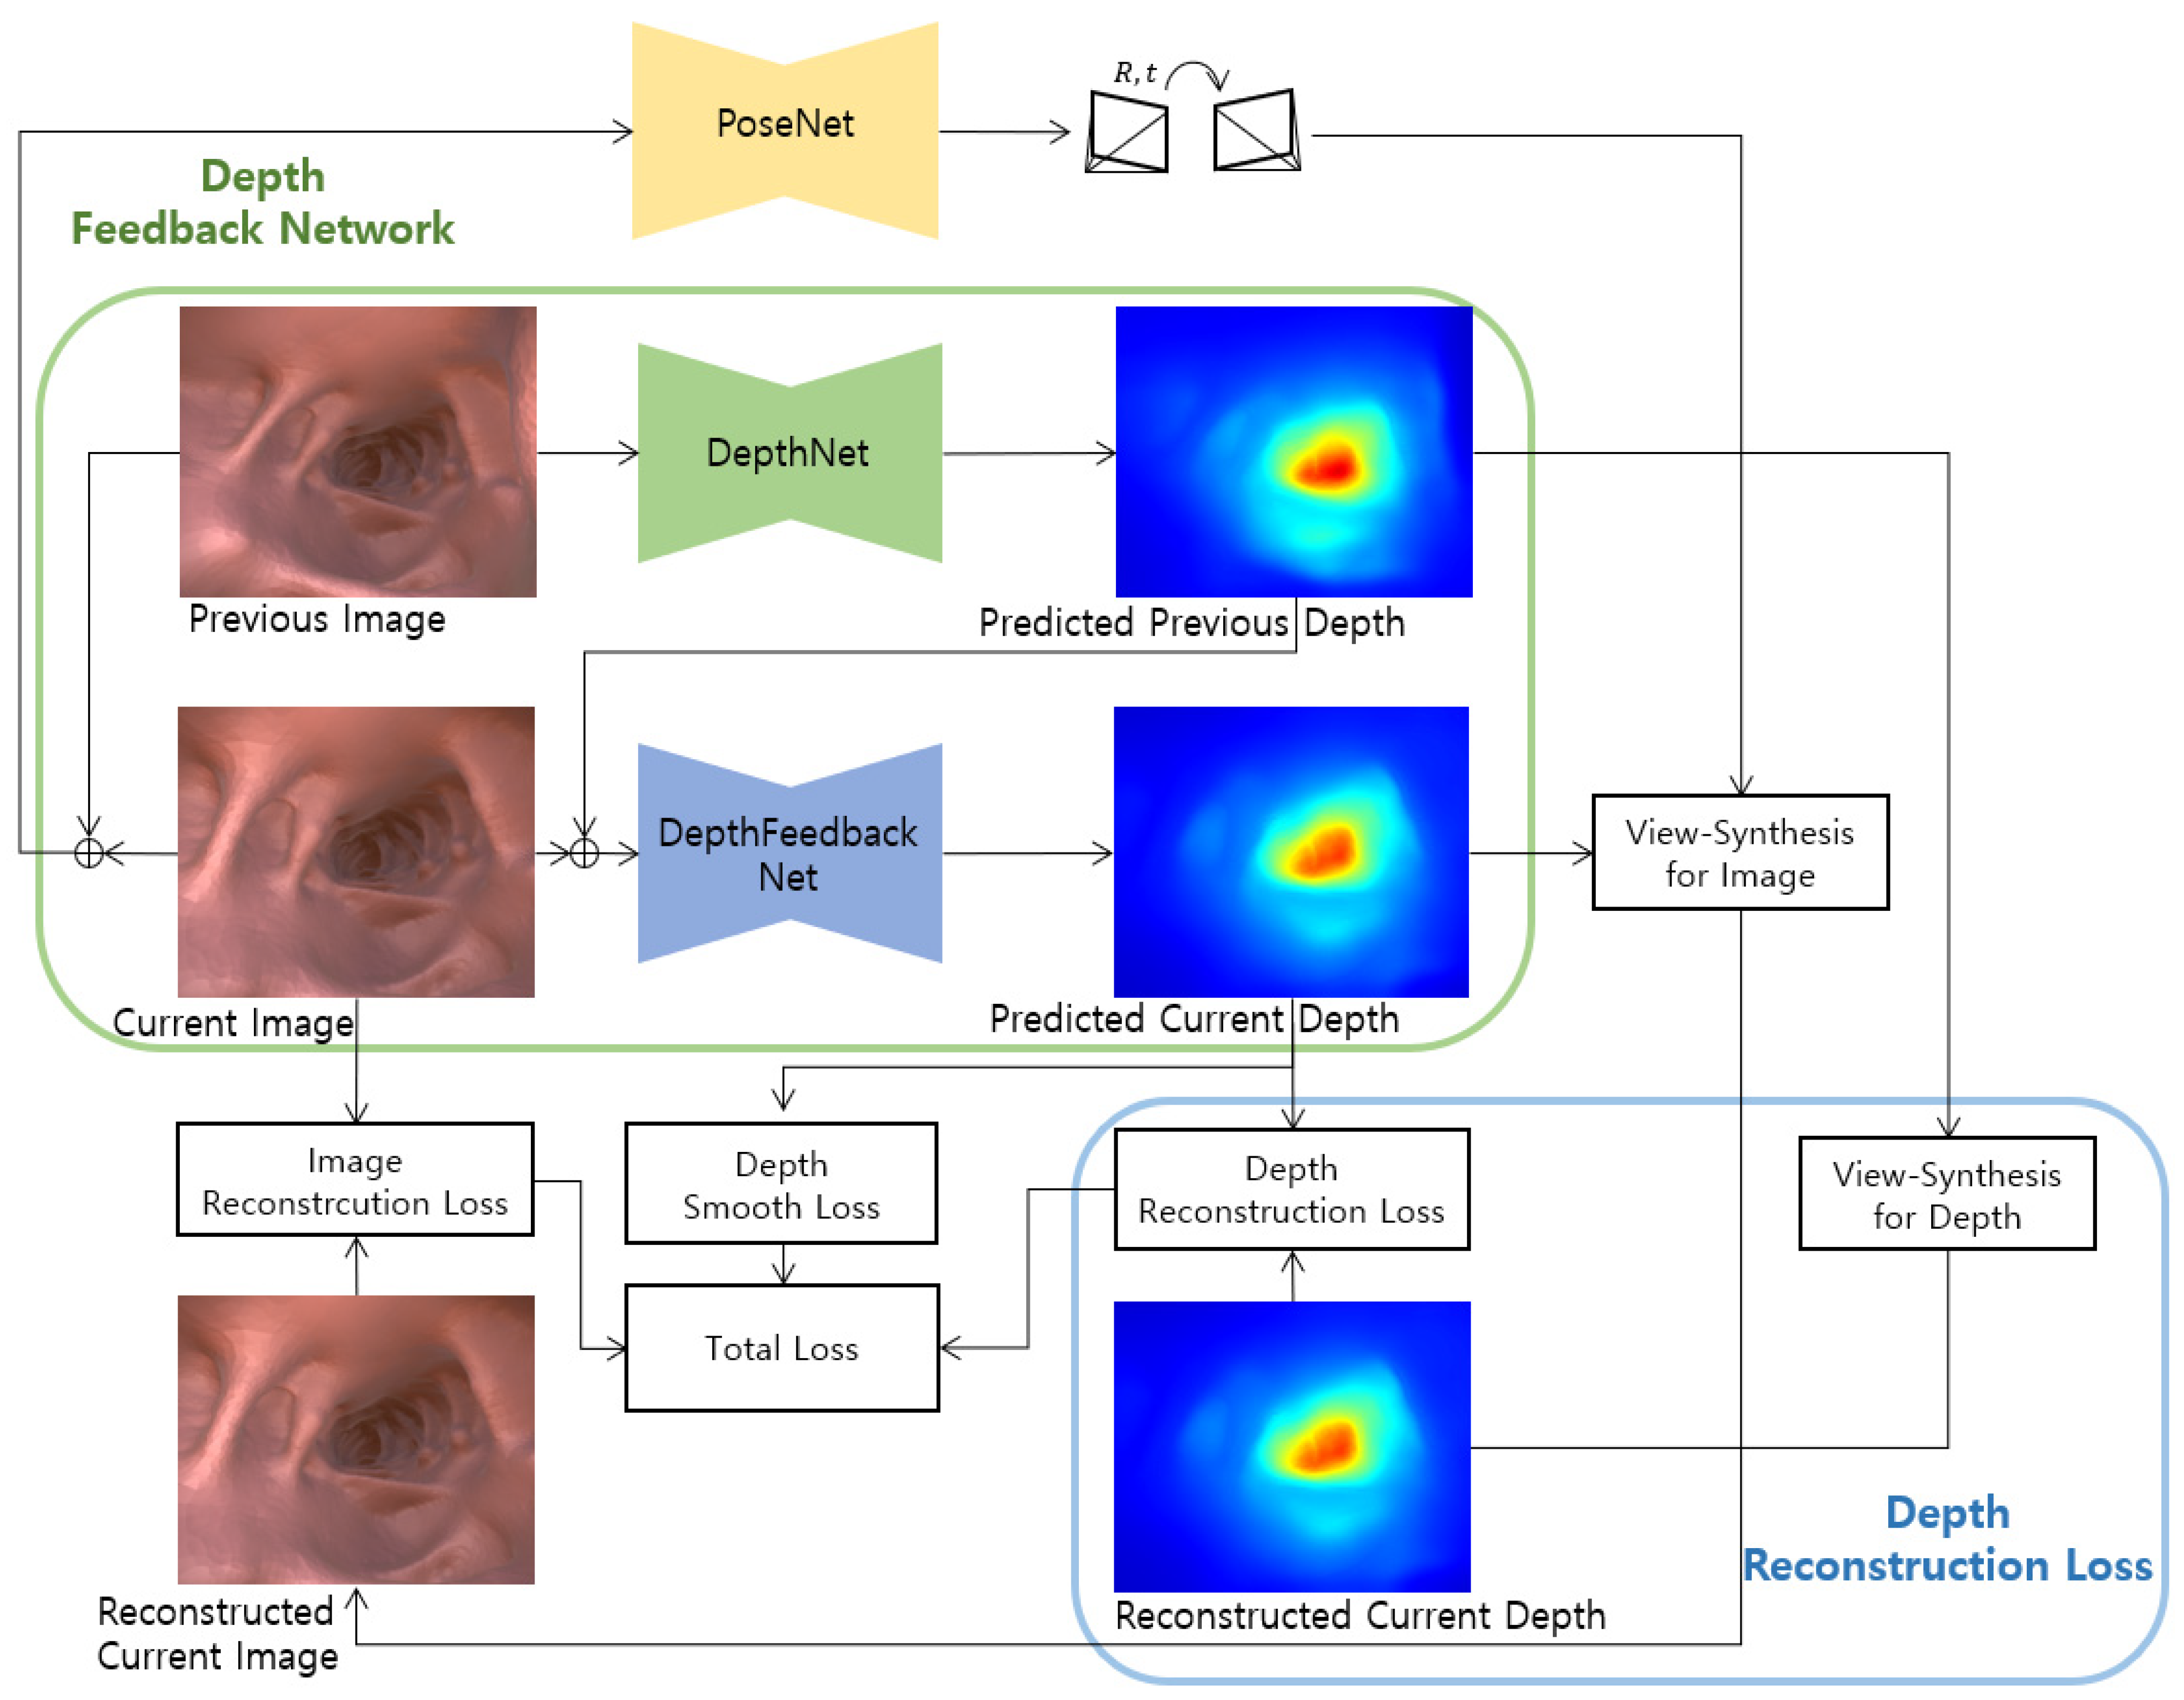

3.1. Self-Supervised Training

3.2. Improved Self-Supervised Training

3.2.1. Depth Reconstruction Loss

3.2.2. Depth Feedback Network

3.2.3. Final Loss